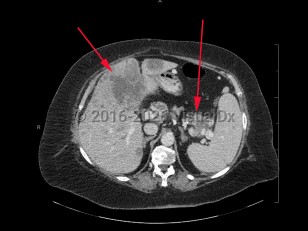

Metastatic pancreatic carcinomaMetastatic pancreatic carcinoma

Polycystic kidney diseasePolycystic kidney disease

Abdominal aortic aneurysmAbdominal aortic aneurysm

Aortic dissectionAortic dissection